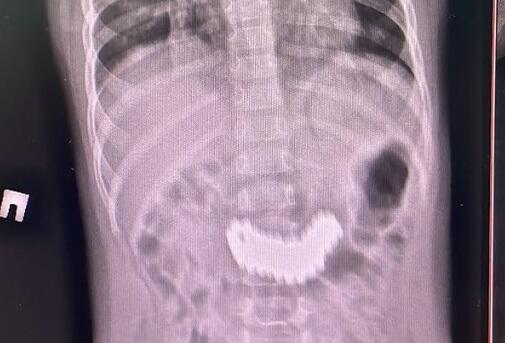

При проведении рентгенографии органов брюшной полости был выявлен конгломерат из множества металлических предметов размером 6,2 × 2,2 см. Ребёнка экстренно госпитализировали для удаления инородного тела. Первоначально специалисты попытались извлечь предметы эндоскопическим путём, однако из-за плотного скопления магнитов это оказалось невозможно. Было принято решение о проведении хирургического вмешательства — лапаротомии и гастротомии. В ходе операции из желудка ребёнка извлекли 105 магнитных бусин", — проинформировали в центре.